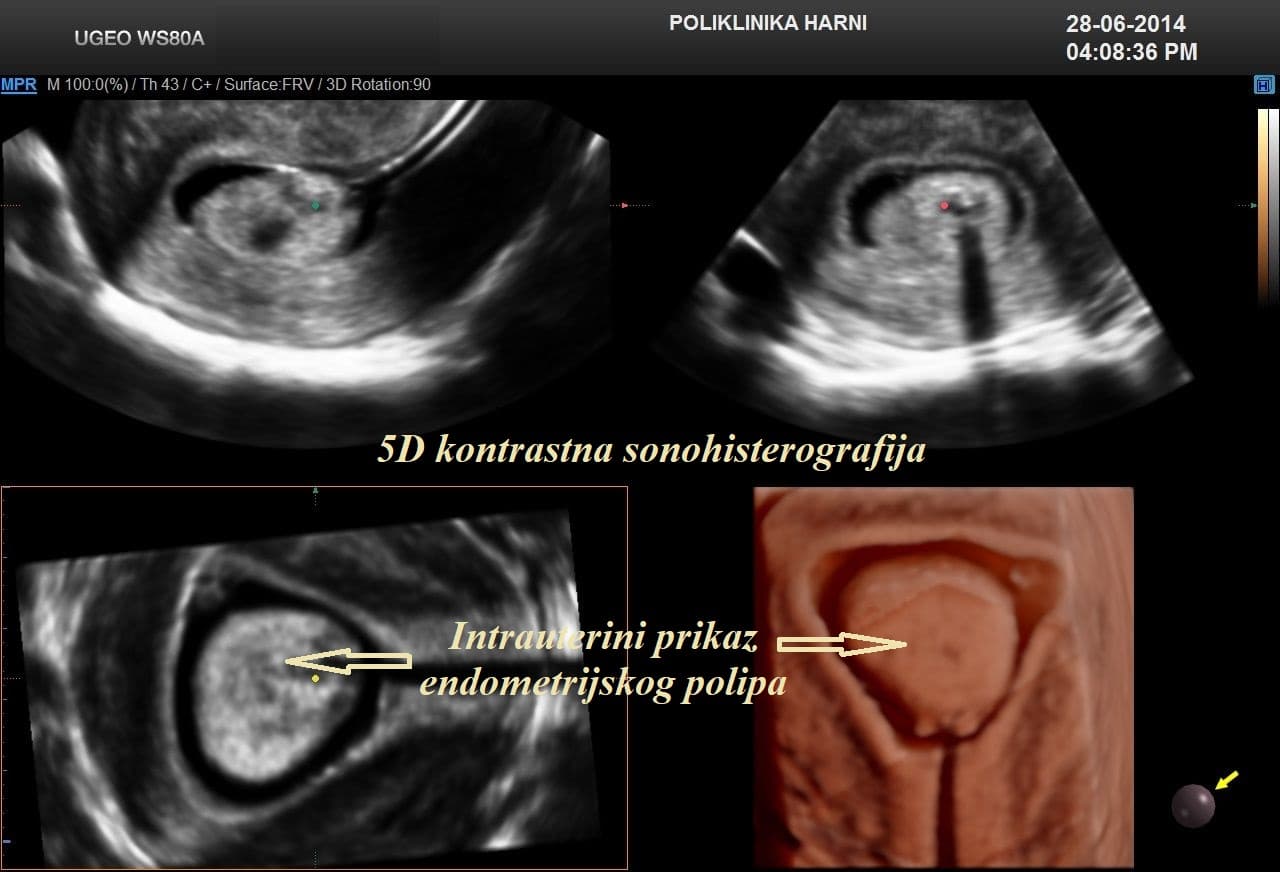

Kontrastni ultrazvukobojenim doplerom i 3D ultrazvukom / Hy-Co-Sy - hysterosalpingo-contrast-sonography sigurna je i učinkovita dijagnostička metoda u procjeni prohodnih jajovoda i od presudnog značenja u obradi neplodnih pacijentica. Provodi se u prvom dijelu menstruacijskog ciklusa nakon potpunog prestanka menstruacijskog krvarenja. Nakon pripreme pacijentice, u kanal vrata maternice se uvodi kateter i ubrizgava kontrast, a potom se prikazuju maternična šupljina, strukture unutar nje, eventualne anomalije maternice i prohodnost jajovoda. Kontraindikacije su trudnoća, krvarenje, akutna zdjelična upala i adneksalni tumor.

Pojava više-dimenzionalnog ultrazvuka omogućuje vizualizaciju ne samo određenih dijelova uterusa nedostupnih dvodimenzionalnom prikazu uslijed položaja uterusa, već i odabir optimalne ravnine kao i načina prikaza sumnjive lezije, a kod 5D ultrazvuka tehnološke inovacije omogućuju dodatne automatske presjeke koji omogućuju slojevitiju sliku i daju dubinu slici ujedno poboljšavajući dijagnostičku točnost. U dijagnostici anomalija uterusa trodimenzionalna rekonstrukcija ima prednost nad dvodimenzionalnim prikazom, te se njegova točnost može mjeriti s točnošću histerosalpingografije.

5D ultrazvučna tehnologija označuje dodatnu, vrhunsku kvalitetu revolucionarnog ultrazvučnog sustava uz automatizaciju tehnike koja više nije apsolutno ovisna o ultrasoničaru, uz najveću kvalitetu dijagnostičkog prikaza na LED monitoru i optimiziranim softverom, koji omogućuje novu slojevitu, dubinsku sliku poput CT prikaza u stvarnoj trećoj dimenziji u svim otvorenim pitanjima kako u ginekologiji, tako i opstetriciji.